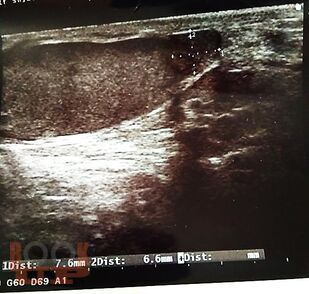

Пособие содержит материал, отражающий современные данные о лечебно-диагностических концепциях основных врождённых и приобретённых урологических заболеваниях взрослых и детей. В пособии раскрыты ключевые позиции, этиологии, патогенеза, классификации, клинических проявлений, диагностики, консервативного и хирургического лечения, возможных осложнений и исходов урологических заболеваний. Сделан акцент на эмбриопатогенез и пренатальную диагностику врождённых аномалий развития органов мочевыводящей системы у детей. Пособие содержит перечень вопросов для самоконтроля, тестовые задания и ситуационные задачи.